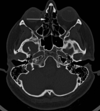

3

Q

A

body of corpus callosum